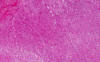

Area 1: The tumor is composed of large, pleomorphic cells with large nucleoli. The tumor cells are densely packed and without any pattern formation. The nuclei are large and there are prominent nucleoli. A moderate amount of cytoplasm is also present. The morphology varies from more spindle appearing to more epithelioid appearing.